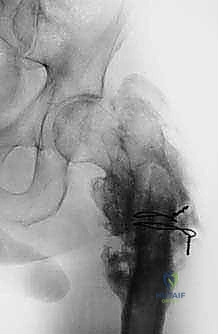

| الأشعة السينية (X-rays) | التقييم الأولي السريع لشكل العظم، اكتشاف الكسور المرضية، وتحديد نمط تدمير العظم. | تعطي الجراح فكرة عامة عن حجم المشكلة وموقعها. |

عندما ينتشر السرطان من عضو آخر (مثل الثدي، الرئة، البروستاتا، أو الكلى) إلى العظام، فإن عظم الفخذ هو أحد أكثر المواقع عرضة لذلك بسبب حجمه وامتداد الأوعية الدموية فيه.

تؤدي هذه الأورام إلى تآكل العظم، مما يسبب ألماً مبرحاً ويجعله عرضة لما يسمى "الكسر المرضي" (انكسار العظم نتيجة إجهاد بسيط جداً بسبب هشاشته الشديدة). في هذه الحالات، يتم استئصال الجزء المدمر واستبداله بطرف اصطناعي لتخفيف الألم فوراً والسماح للمريض بالمشي مجدداً.